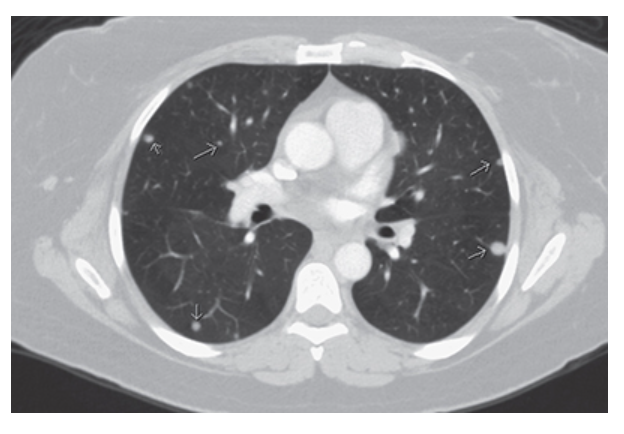

Pulmonary Metastatic Disease. Multiple peripheral pulmonary metastases (arrows).